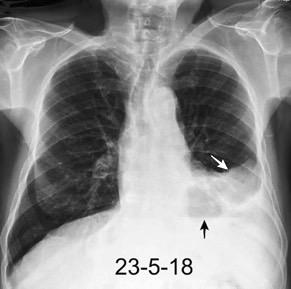

Marzo 2014: Perforación longitudinal distal secundaria a episodio de vómito (síndrome de Boerhaave). Derrame pleural izdo. que evoluciona a empiema.

Wang C-T et al. Tension hydropneumothorax in a Boerhaave syndrome patient: A case report . World J Emerg Med, 2021. Katabathina V et al. Nonvascular, nontraumatic mediastinal emergencies in adults:a comprehensive review of imaging findings. Radiographics. 2011.